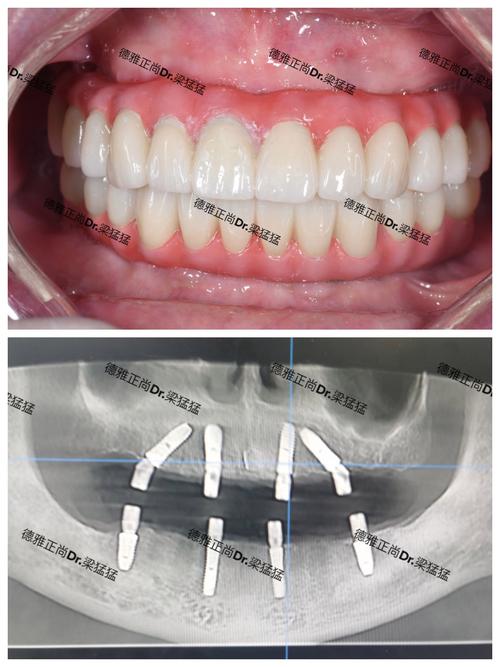

- 优点: 包含大量科研文献中的图片,有学术背景,能看到临床应用场景(如X光片、口内照)和结构示意图。

- 结合学术资源: 在 PubMed 上搜索特定品牌型号,查找相关研究文章中的图片(尤其是结构示意图和临床X光片)。